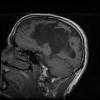

Varón, 33 años, portador de implante coclear izquierdo. IABVD. Dos semanas antes de consultar, de forma brusca nota debilidad de ESD. No refiere cefalea ni otra clínica. Acude a urgencias por este motivo donde presenta...

Caso completo | PDF

Neurología: Epilepsia | InfecciosasEtiología: Infecciosas / inflamatoria / desmielinizanteDiagnóstico final: Crisis focal con generalización secundaria. Toxoplasmosis cerebral. SIDA.Nivel de certeza: